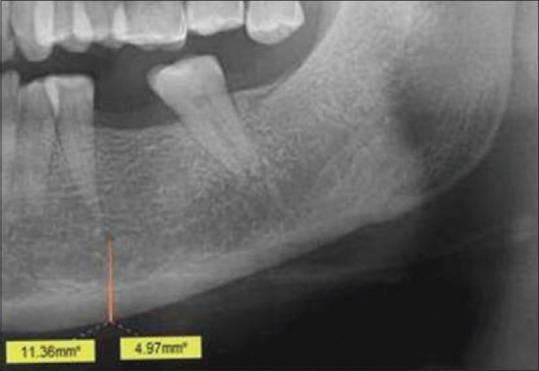

Osteoporosis is a specific condition which is characterized by low bone mineral density (BMD) and deterioration of bone structure resulting in an increased susceptibility to fractures. It contributes to a great deal of morbidity and mortality, and is a large burden to the healthcare system, especially in the case of the elderly population. In the last four decades, a plethora of studies have reported characteristic oral radiographic findings in the early stages of osteoporosis, suggesting the possible use of oral radiographic signs for the early detection of the condition. Digital orthopantomographs (OPGs) are usually taken for the screening of dental patients during routine dental evaluations. These radiographs and the characteristic changes seen on them may have a significant role in the screening for initial osteoporotic changes. A number of precise radiomorphometric indices of the mandible have also been developed to allow quantification of the mandibular bone mass for identification of the initial signs of osteoporosis. The present review focuses on the possible role of panoramic radiographs in the initial screening for osteoporosis in dental clinics in high-risk groups.

骨质疏松症是一种特殊的病症,其特征是骨矿物质密度(BMD)低且骨结构恶化,导致骨折易感性增加。它导致大量的发病和死亡,给医疗保健系统带来巨大负担,尤其是在老年人群中。在过去的四十年里,大量研究报告了骨质疏松症早期阶段典型的口腔放射学表现,这表明口腔放射学征象可能用于该病症的早期检测。在常规牙科评估期间,通常会拍摄数字化曲面断层片(OPG)以筛查牙科患者。这些X光片及其上所见的特征性变化可能在初步骨质疏松症变化的筛查中发挥重要作用。还开发了一些精确的下颌骨放射形态计量学指标,以便对下颌骨质量进行量化,从而识别骨质疏松症的初始迹象。本综述重点关注全景X光片在高危人群牙科诊所骨质疏松症初步筛查中的可能作用。